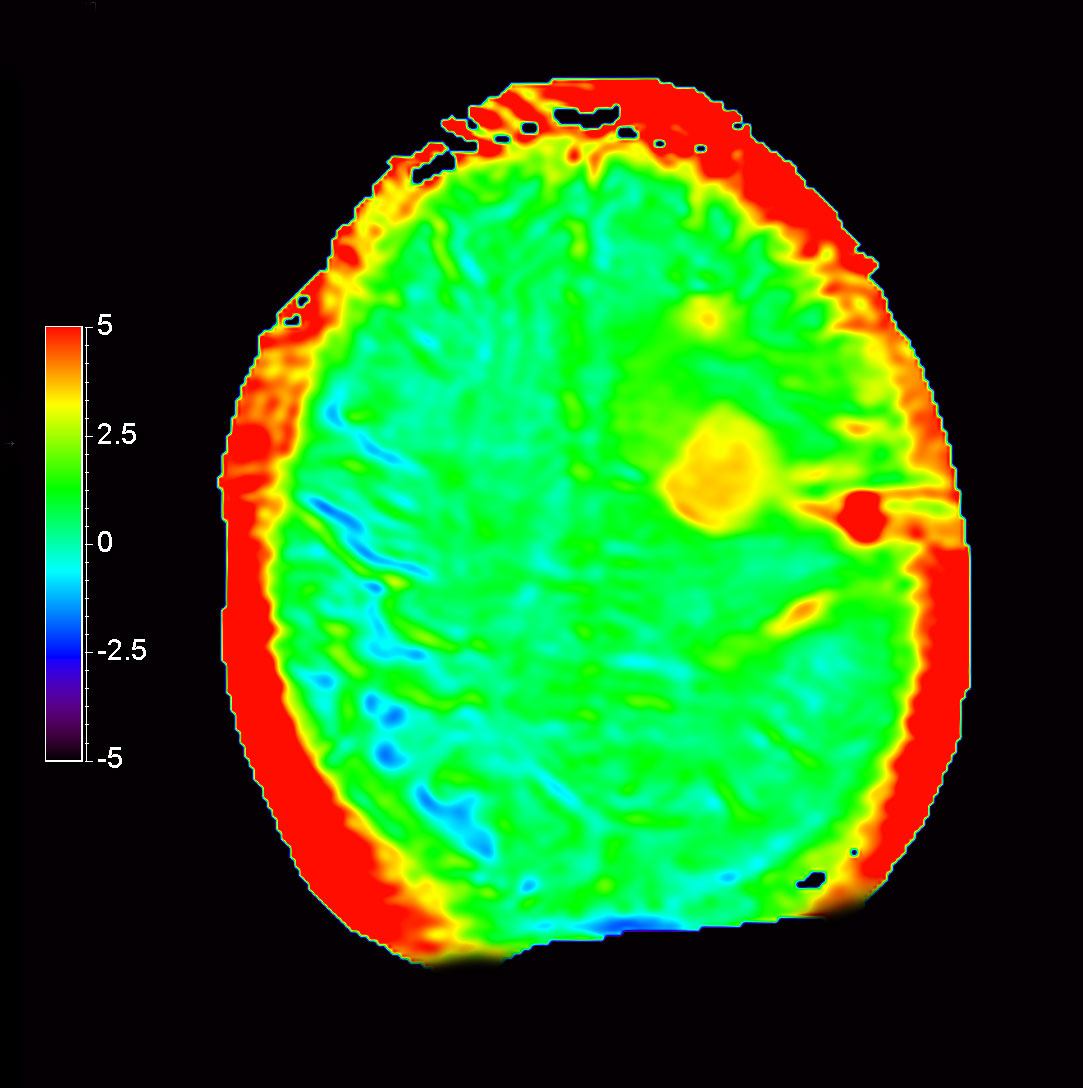

Axial T2* Perfusion - TO

-

Axial T2* Perfusion - TTP

Axial T2* Perfusion - rCBF